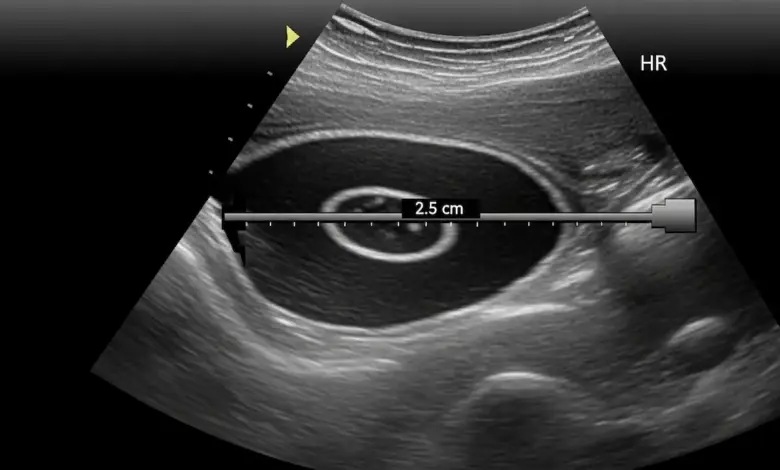

- Ultrassonografia: boa para diferenciar líquido de tecido sólido e avaliar estruturas superficiais.

- Ressonância magnética: é o exame mais completo para ver labrum, manguito, cistos paralabrais e possíveis compressões nervosas.